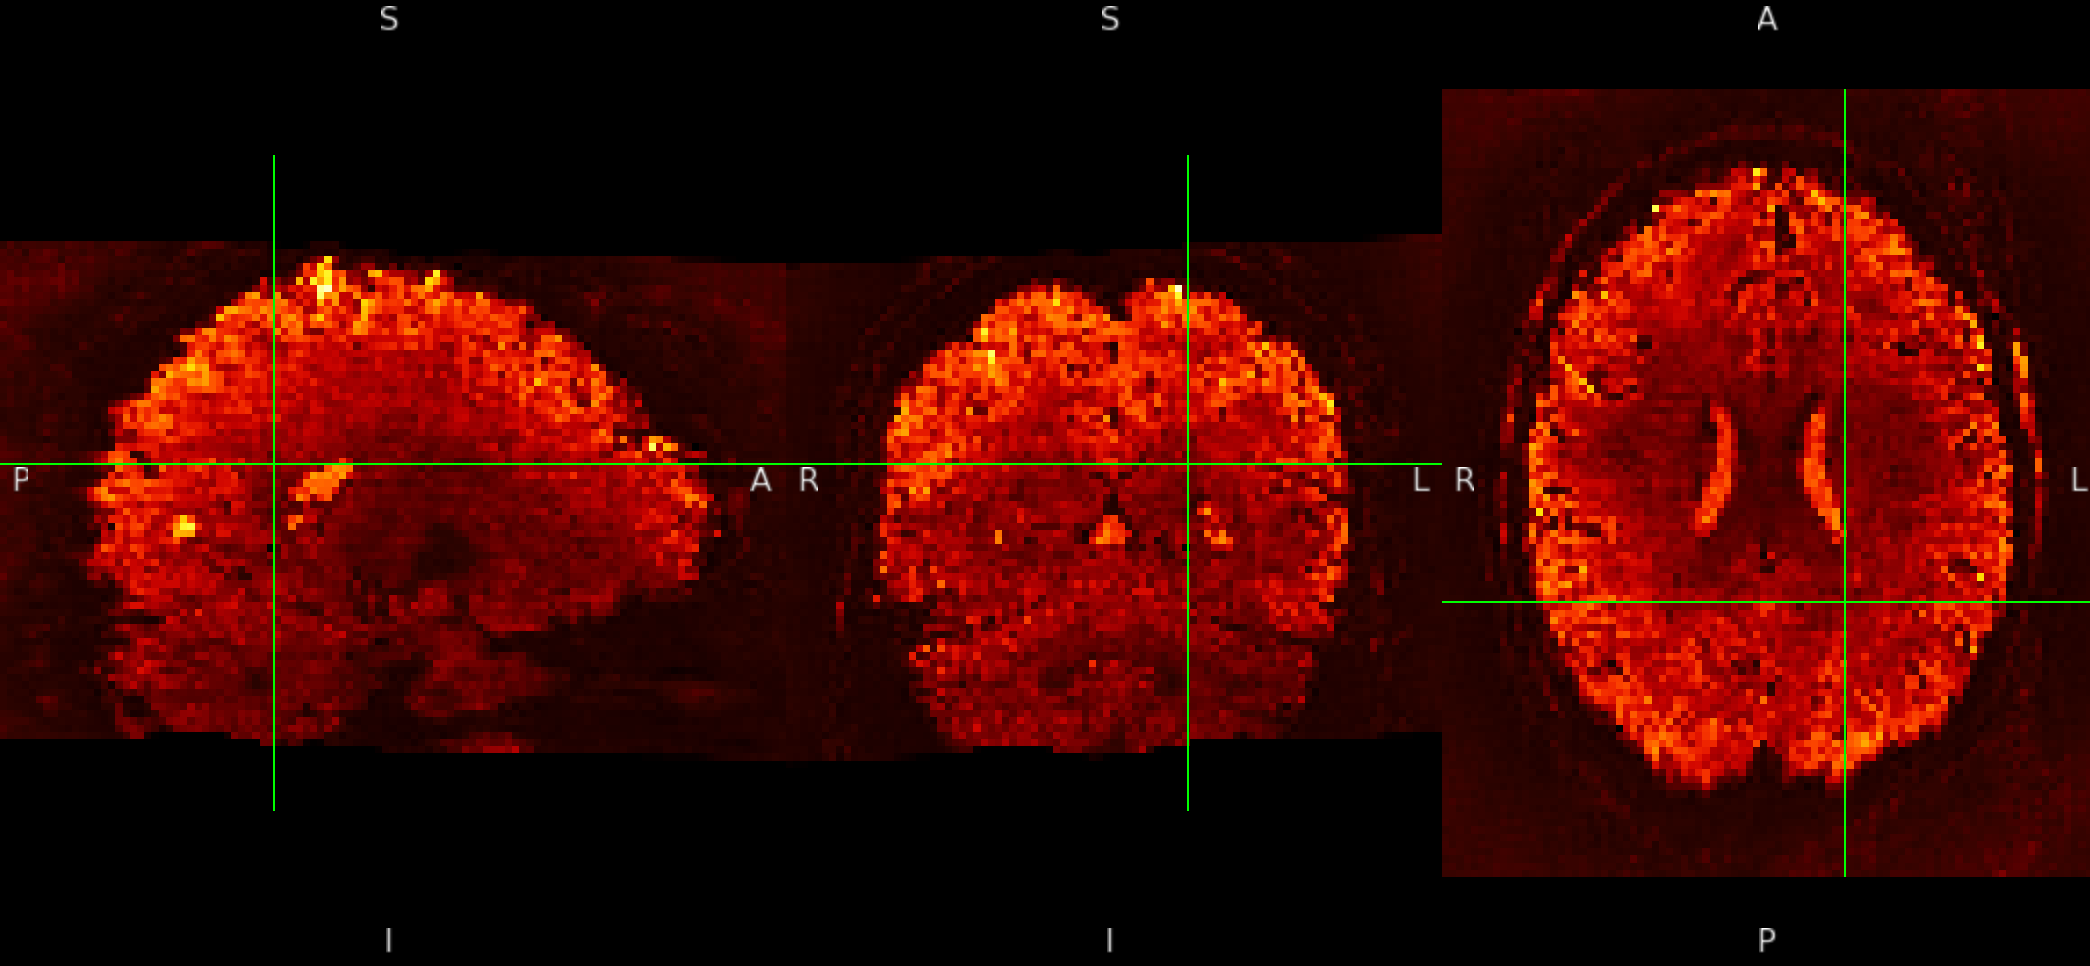

And although it is not visible for the SE sequence in MNI152NLin6Asym-res2, it is visible outside the brain in the ME sequence in MNI152NLin6Asym-res2

SE sequence in MNI152NLin6Asym-res2

ME sequence in MNI152NLin6Asym-res2